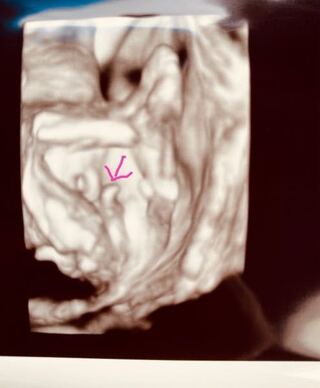

15wのエコーでちんちんらしきものが 見えました へその緒ではなさそ 妊娠 教えて Goo

4dエコー性別 股を開いた写真なんですが男の子にも女の子にも見えます 出産 教えて Goo

みなさん教えてください こちらの4dエコーでの 黄色丸部分は男の子の Yahoo 知恵袋

4dエコーです どうみてもシンボルですよね 23周で今日撮ってきた4d 出産 教えて Goo

19週の時の4dエコー写真です 写っている突起物は男の子のも Yahoo 知恵袋

男の子 女の子どちらだと思いますか 4dエコーです このお股から背中 妊娠 教えて Goo